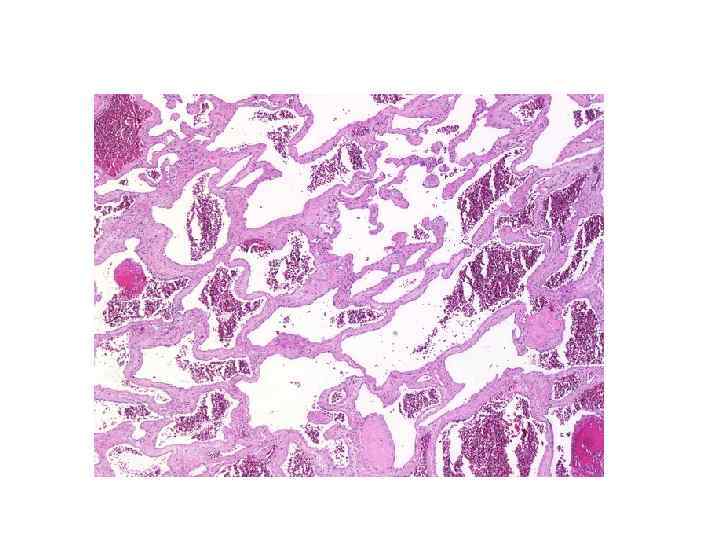

Капиллярная телеангиэктазия • 20% сосудистых мальформаций ГМ, обнаруженных на аутопсиях • Локализация: мост, мозжечок, спинной мозг